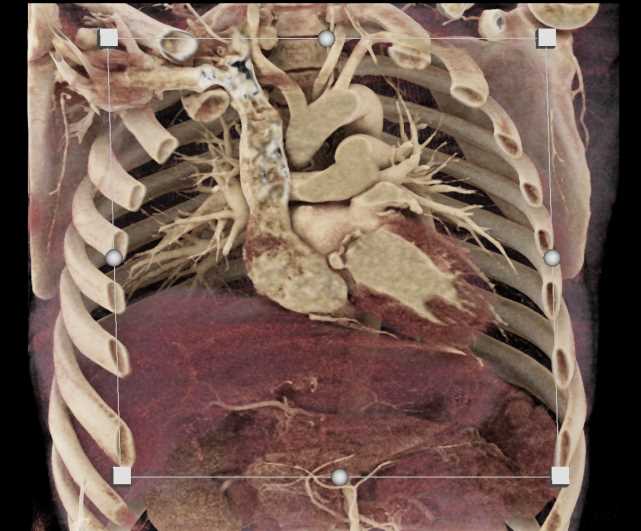

Aortic Valve Repair